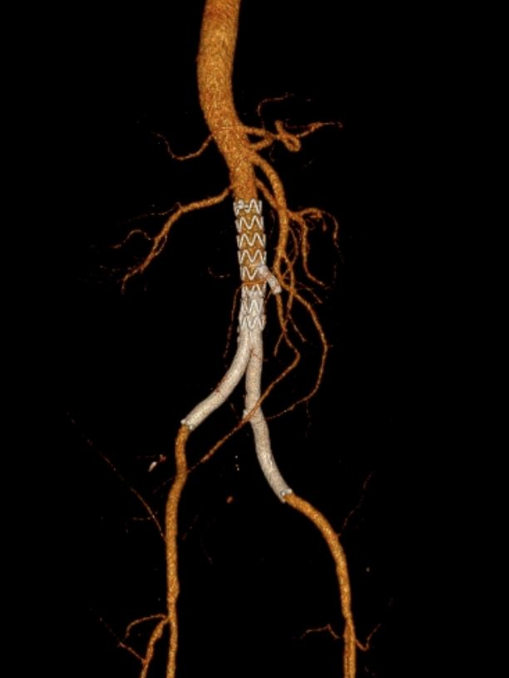

通过覆膜支架重建主动脉分叉治疗主髂动脉病变。

操作路径:可经股动脉或肱动脉入路,需双侧支架对吻释放(模拟解剖分叉)

治疗策略:复合手术(双侧股动脉切开取栓 + CERAB),兼顾血栓清除与长期血管重建。

左侧肱动脉入路,主髂动脉造影

双侧股动脉切开,经股动脉7F Fogarty导管取栓

术后结果:ABI改善,症状缓解,无围术期并发症